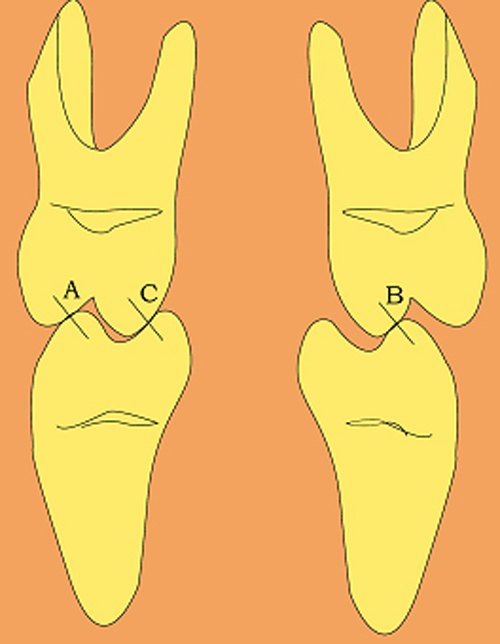

En ciertas áreas del saber humano, el lenguaje confuso o criptográfico Muchas son las técnicas elaboradas para lograr un desgaste selectivo, y numerosos autores han expuesto en su momento variadas formas de lograr una función oclusal fisiológica mediante el ajuste de la misma. Han pasado años desde entonces y, sin embargo, aún hoy, un altísimo porcentaje de profesionales “navega” por el mar de la confusión oclusal, dada la diversidad de conceptos y escuelas, sin lograr arribar a costa alguna donde poder anclar un conocimiento sólido sobre cómo tratar la oclusión Ya se esté realizando una simple obturación, endodoncia, incrustación, radectomía u ortodoncia, la lógica pocas veces, en la mayoría de los casos, vincula un tratamiento con otro, siendo el resultado final el mismo caos inicial; enmascarado por mucho tratamiento profesional. El ajuste oclusal es un medio inicial de proveer al sistema enfermo de: Dicha técnica, que puede ser terapéutica en sí misma; consta de dos etapas, a saber: 1) Ajuste Oclusal por Adición Mediante el estudio de la guía anterior, encargada de efectuar las Disclusiones durante las excursiones mandibulares, podremos observar si ésta es funcional o no. • Marcas de carácter continuo, si en ese recorrido se produce la Disclusión de los sectores posteriores y todo marcha correctamente. FIG 1-2 Si por el contrario observamos: • Marcas de carácter discontinuo, significa que dicha Disclusión se está efectuando por medio de una pieza dentaria posterior a la guía anterior. FIG 3-4-5 (FIGS. 3, 4 Y 5). En la figura 6 las flechas indican, en un caso clínico de análisis oclusal, la presencia de marcas discontinuas que indican Interferencias en Propulsiva. FIG 6-7 Y por último, si existieran: • Abrasiones de las áreas discluyentes en las áreas de diagnóstico de la guía anterior, deberemos aportar material a dicha zona para no permitir el choque lateral de las piezas posteriores (Ajuste Oclusal por Adición) En las imágenes 11 y 12 podemos observar la adición de composite en la punta de un canino derecho, previa la observación de la Faceta Parafuncional remarcada durante el análisis oclusal en el articulador. (FIGS. 8 A 12). 2) Ajuste oclusal por Sustracción o Desgaste Habiendo cumplido ya con la verificación de la funcionalidad de la Guía Anterior, comenzamos los desgastes en céntrica, a fin de lograr un único arco de cierre, guiado eficazmente por la Guía Anterior; es decir: la coincidencia entre Oclusión Habitual y Oclusión en Relación Céntrica. En este caso, intentar gastar dichos puntos, de ser posible sólo en las cúspides de corte o no fundamentales: • Crestas Triangulares Internas, Cúspides Vestíbulares Superiores • y un poco de las Crestas Triangulares Internas, Cúspides (FIGS. 13 A 16). Si la deflección es hacia el lado opuesto, se invierten los desgastes. En las migraciones hacia adelante, las únicas razones posibles están en los puntos estabilizadores (FIG. 17); es decir: -Vertientes Distales de los Rebordes Marginales, Triangulares (FIG 17) (FIG 18 A-B-C-D) Obsérvese cómo, en una boca prácticamente entera, comienzan a “desmoronarse” prismas adamantinos (FIG. 19), como consecuencia de un punto prematuro de contacto, ubicado en la posición de un estabilizador, que provoca la discrepancia horizontal postero-anterior causante de dicho efecto (FIG. 20). FIG 19-20 Dicho punto, será necesario ajustarlo antes de cualquier tratamiento en la zona ¿Cuáles serían las consecuencias si esos incisivos fueran implantados tal como es frecuente observar en múltiples congresos y cursos de implantología, donde el tema de la oclusión no es más que un cuadro polifacético y anecdótico? 14 15 16 17 Todo producto del adelantamiento mandibular Realizados ya los desgastes en céntrica, obteniendo de esta manera un único arco de cierre, es decir, oclusión en relación céntrica, debemos realizar el ajuste de las excéntricas, apoyando la acción de la guía anterior, para lo FIG 22 a. De un lado a otro de un mismo maxilar, la imagen es especular, o sea invertida. b. En hemimaxilares cruzados, la imagen es idéntica. Allí donde existan colisiones entre cúspides, se deberá crear un surco para que dicha cúspide antagonista migre a su través, tanto en el lado de no trabajo, como en el de trabajo y en el de propulsión. FIG 23 Es importante conservar esta parte del surco, ya que si no existieran, los contactos entre cúspides serían en superficie y no puntiformes (fig. 24). FIG 24 1. Obtener un único arco de cierre con coincidencia entre oclusión habitual y relación céntrica. 2. El cierre mandibular debe ser recibido sólo por la tabla premolar-molar. 3. Durante las excursiones funcionales es la guía anterior la que debe sufrir las fuerzas laterales. 4. De cumplirse estas dos premisas debemos obtener libertad de desplazamiento (no confundir con libertad en céntrica) a las piezas posteriores mediante la creación de surcos disclusivos. Examinadas ya las posibles migraciones mandibulares y los desgastes o aposiciones necesarios para poder ocluir en céntrica, es fundamental recordar que, previamente a todo tipo de ajuste, se ha hecho necesario ubicar a la mandíbula en relación céntrica. Para ello debemos utilizar el propio funcionalismo muscular 22 FIG 25 Y esto no significa otra cosa que: piezas dentarias estables en todos los planos del espacio, ATM centrada en la cavidad glenoidea, periodontos sin tensión, músculos en la dimensión de elongación adecuada para un fisiologismo Paz absoluta en la intimidad del Sistema Estomatognático. Y así, como corolario final, es posible establecer una regla de oro similar en importancia a la conocida formula: Forma = Función Ésta es: FIG 26 FUNDAMENTOS NEUROFISIOLÓGICOS DEL REGISTRO DE OCLUSIÓN EN RELACIÓN CÉNTRICA ( ORC) MEDIANTE EL USO DE LAMINILLAS DE LONG CUADRO

Si la deflección es por ejemplo hacia la izquierda, observaremos que las únicas causas posibles son por contacto en los puntos de estabilidad vestíbulo-palatina A o C derechos o bien en el B izquierdo.

Es decir:

(Punto A) y Crestas Triangulares Internas, Cúspides Linguales Inferiores (punto C), del lado derecho.

Estampadoras (punto B), del lado izquierdo .FIG 13-14-15-16